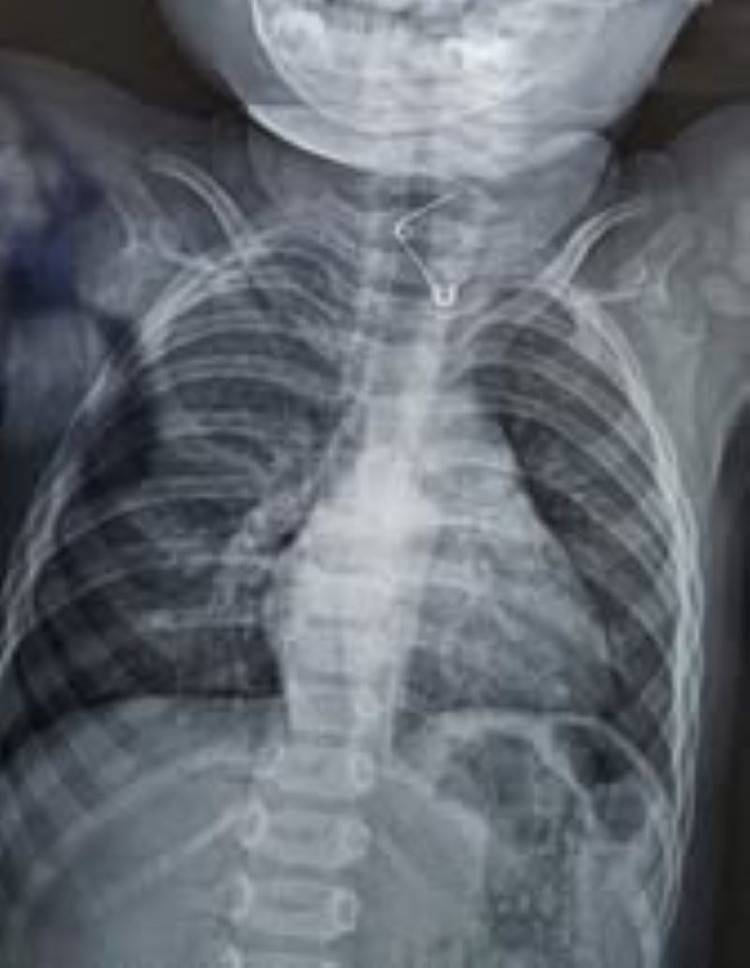

Cây kim băng trong thực quản bé trên phim chụp - Ảnh BVCC

Tại Khoa Cấp cứu, qua thăm khám và hình ảnh nội soi, bác sĩ phát hiện cây kim băng dài khoảng 3 cm, đã bung ra thành hình chữ L và đầu nhọn đang ghim vào thành thực quản – gây nguy cơ thủng, chảy máu và nhiễm trùng rất cao.